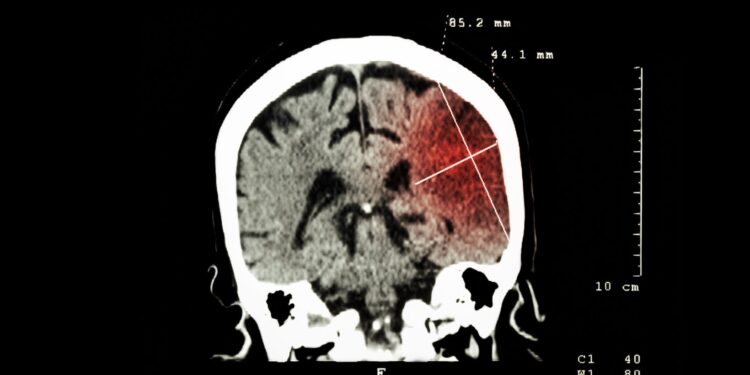

뇌혈관이 막혀 발생하는 허혈성 뇌졸중 증상이 나타난 후 48시간 이내에 신경 보호 신약 물질을 투여하면 뇌세포 보호와 회복 효과를 얻을 수 있다는 무작위 대조 임상시험 결과가 나왔다.

이 결과는 중국 베이징 톈탄병원 임상시험센터 리슈야 박사팀이 중국 내 32개 의료 기관에서 허혈성 뇌졸중 환자 998명을 대상으로 실시한 임상시험의 결과로 최근 미국 뉴올리언스에서 열린 ‘국제 뇌졸중 학회 2026′(International Stroke Conference 2026)에서 발표됐다.